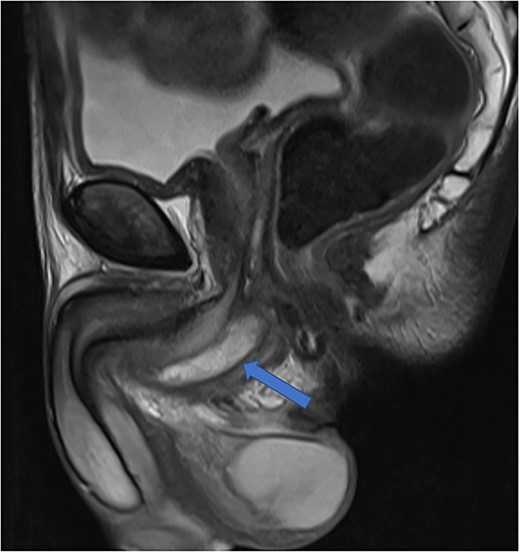

Imaging was suggestive of an infected Cowper’s syringocele. As the patient was clinically stable, a trial of antibiotic therapy was suggested. Repeat MRI a week later showed that the collection had extended into the corpus spongiosum, which now appeared expanded with the fluid density signal (Fig. 1). On a review, the urethral catheter was thought to be impairing potential drainage of the collection. It was removed, and a suprapubic catheter was inserted. Ultrasound guided aspiration failed to drain a significant amount of pus, which also grew S. anginosus. There was also radiological suspicion of a colovesical fistula. The patient was reviewed by the colorectal surgeons, who felt that as there were no other symptoms relating to the fistula, and the patient was physiologically frail, and defunctioning of the bowel would be inappropriate. Likewise, the patient was deemed too frail for any surgical management of the collection. He was discharged after a total of 6 weeks’ antibiotics. Repeat MRI 4 months later (Fig. 2) showed a smaller but persistent collection.

Case 1: sagittal and coronal T2-weighted images showing the collection (blue arrow) inferior to the prostate, and involving the corpus spongiosum (yellow arrow).